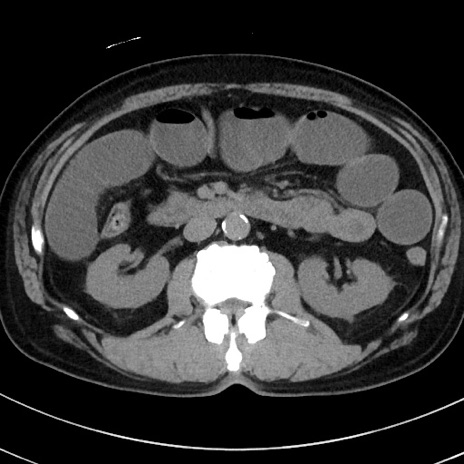

冠状断像

【症例】70歳代 男性

【主訴】腹痛・嘔吐

【現病歴】昨晩より、嘔吐・腹痛あり。今朝になっても嘔吐あり。来院。

【既往歴】心臓バイパス手術、開腹胆摘、腸閉塞

【身体所見】BP 107/71mmHg、HR 116/min、腹部:平坦、軟、下腹部に軽度圧痛あり。反跳痛なし。

【データ】WBC 15100、CRP 0.32